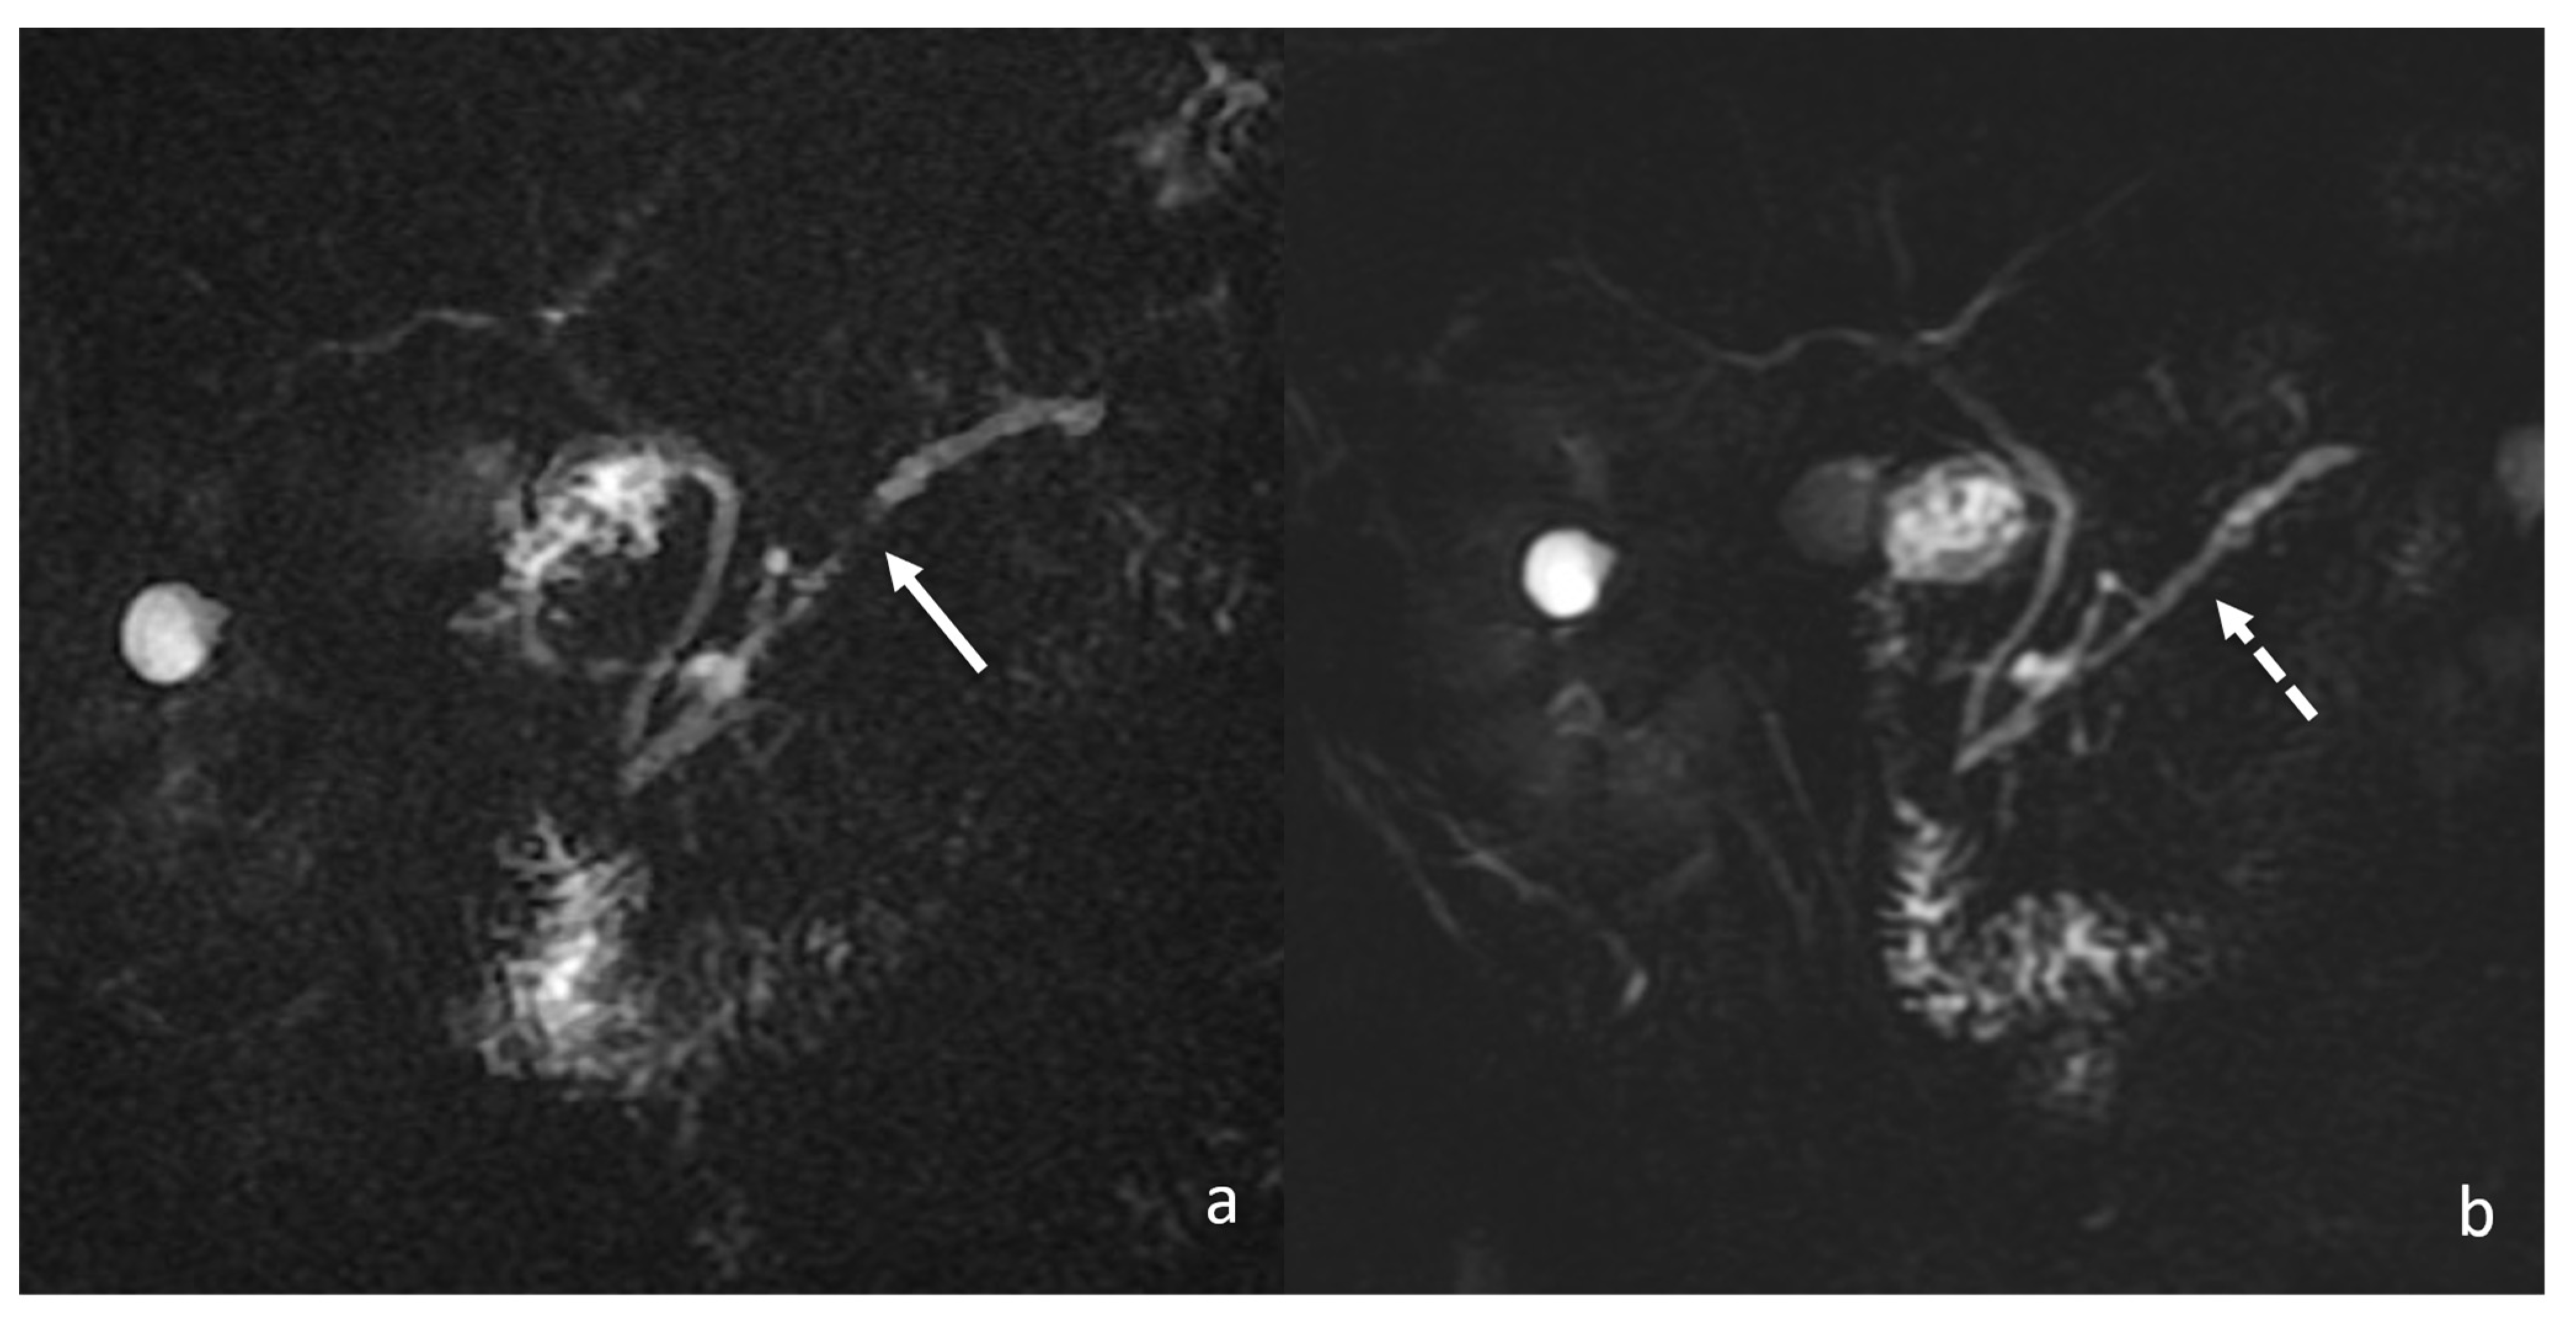

2. Case Report